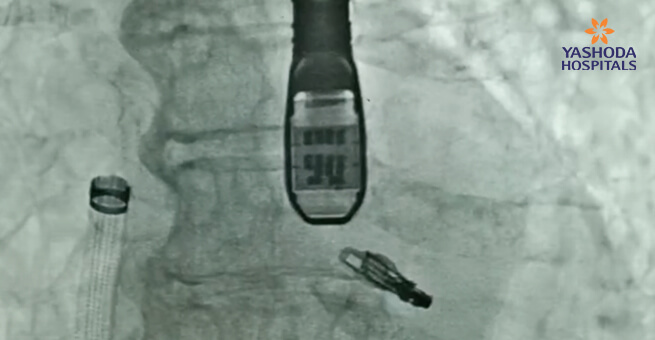

تم إدخال امرأة تبلغ من العمر 86 عامًا إلى مؤسستنا وهي تعاني من ارتجاع تاجي حاد. نظرًا لارتفاع مخاطر خضوعها لجراحة القلب التقليدية، اختار الفريق الطبي إجراء إصلاح من الحافة إلى الحافة عبر القسطرة (TEER) باستخدام MitraClip كنهج علاجي. شكلت دراسة الحالة الافتتاحية هذه علامة بارزة في ممارستنا الطبية، مما دفعنا إلى التخطيط والتنفيذ الدقيقين لتنفيذها بنجاح.

يعد إجراء MitraClip بمثابة تدخل جراحي بسيط مصمم خصيصًا لمعالجة خلل الصمام التاجي. يستخدم الممارسون الطبيون أنبوبًا رفيعًا، يُعرف باسم القسطرة، للوصول إلى الصمام التاجي أثناء العملية. يتم إدخال هذه القسطرة بعناية في الوريد الموجود في الطرف السفلي للوصول إلى منطقة القلب.

يتم إدخال مقطع صغير وتثبيته على الصمام جراحياً، بهدف تعزيز إغلاق الصمام التاجي. يهدف هذا التدخل إلى استعادة الدورة الدموية الفسيولوجية داخل نظام القلب. على عكس الطرق الجراحية التقليدية، فإن تقنية MitraClip تلغي الحاجة إلى بضع الصدر أو التوقف المؤقت لنشاط القلب، لأنها لا تتطلب فتح تجويف الصدر. تتيح أبعاد المقطع إمكانية الإدخال عبر إجراء يعتمد على القسطرة.